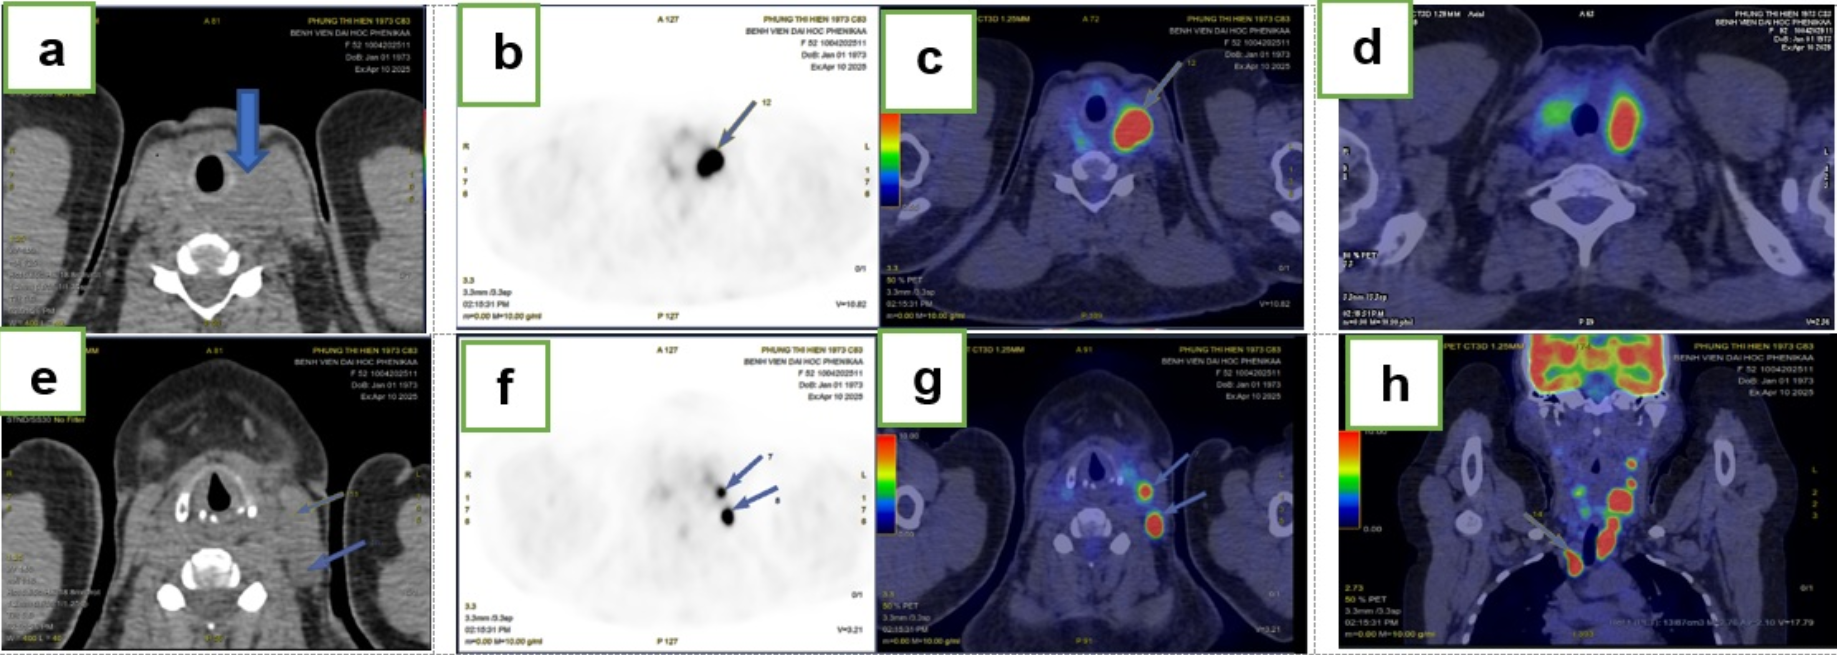

The postoperative course was uneventful, and the patient was discharged on day 7. Positron-emission tomography/CT performed before chemotherapy demonstrated stage IIE disease (Figure 6). Seven months after the function-preserving lobectomy, she had completed several cycles of R-CHOP, her thyroid function remained normal (TSH 1.63 mIU/mL; T₃ 159.9 ng/dL; free T₄ 1.2 ng/dL), her voice was normal, and there were no clinical or biochemical signs of hypocalcaemia (total serum calcium 2.49 mmol/L).

Post-operative staging with ¹⁸F-FDG PET/CT.a-d) Axial, sagittal, and coronal PET/CT fusion images showing multiple foci of intense fluorodeoxyglucose (FDG) uptake in the residual right thyroid lobe (SUVmax: 13.6), indicating extranodal involvement. e-h) Images demonstrating pathological FDG uptake in several cervical (levels II, III, Vb left; bilateral level IV) and mediastinal (bilateral level II) lymph nodes (SUVmax: 24.8), confirming nodal involvement. The findings are consistent with stage IIE disease.